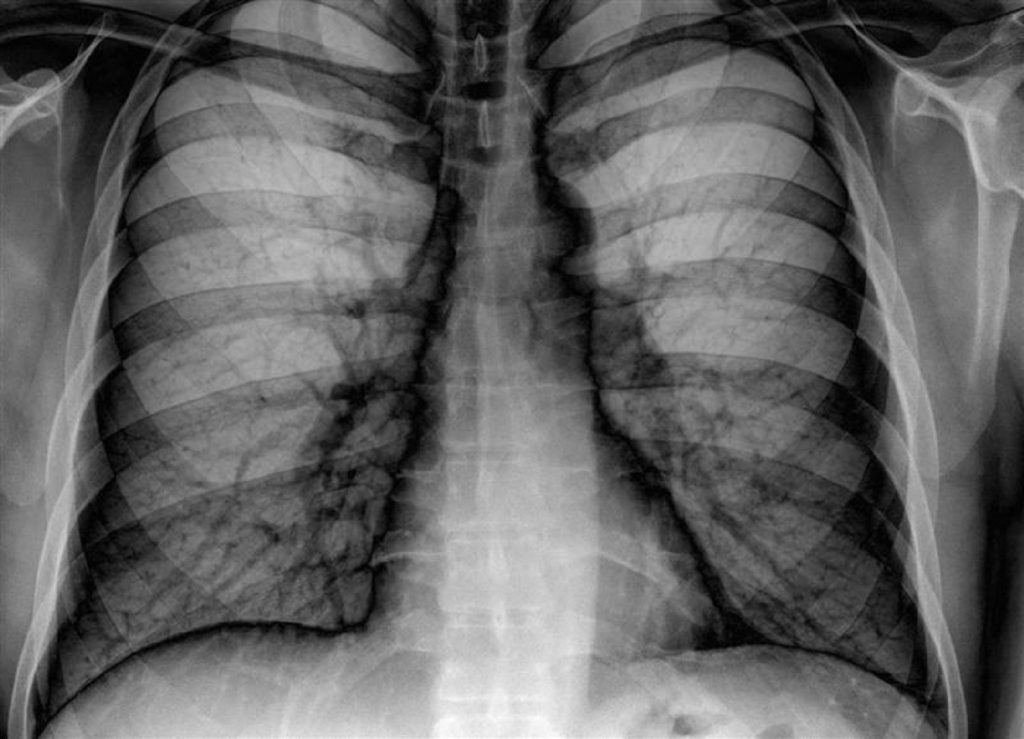

Πώς μπορείτε να σταματήσετε το κάπνισμα;